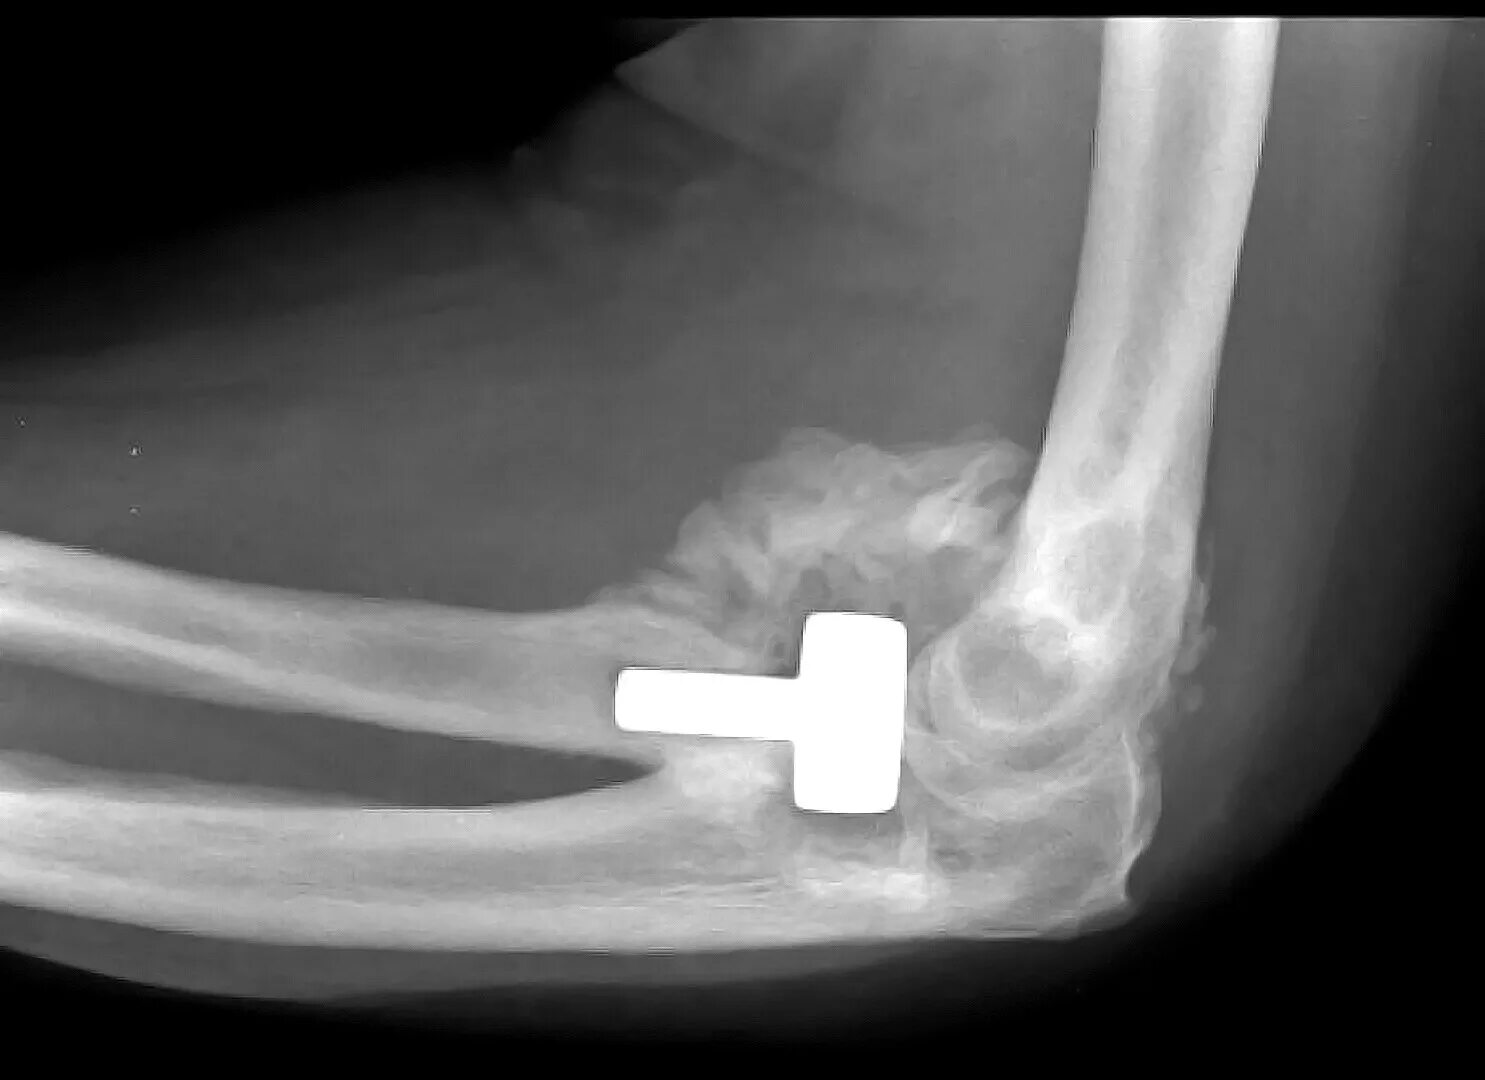

Оссифицированный миозит